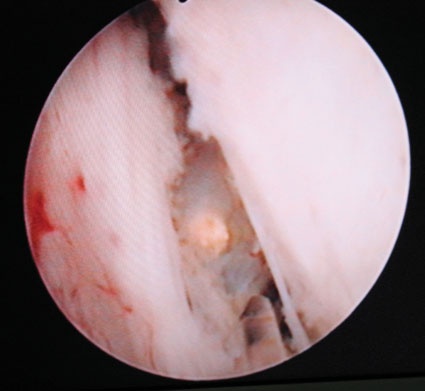

Eines dieser Verfahren ist die sogenannte Holmiumlaserenukleation (HoLEP) der Prostata. Hierbei handelt es sich analog zur TUR-P um ein trans¬urethrales Operationsverfahren. Im Gegensatz zur TUR-P wird bei der HoLEP das obstruktive Prostatagewebe bis zur sogenannten chirurgischen Prostatakapsel ausgeschält, in der Harnblase abgeworfen und schließlich mittels eines Spezialinstruments (Morcellator) in der Harnblase zerkleinert und zur Gewebe-Asservierung und histologischer Aufarbeitung abgesogen.

Während des Schneidens mit dem Holmium-Laser führt die abstrahlende Wärme zu einer zeitgleichen Koagulation kleiner und mittelgroßer Gefäße. Hierdurch ist der Eingriff sehr blutungsarm. Entsprechend können auch sehr große Prostatae (>antikoagulative Medikation 100 cm3) erfolgreich behandelt werden, ohne das Risiko einer signifikanten Blutung mit konsekutiver intravasaler Einschwemmung von Spülflüssigkeit fürchten zu müssen. Weiterhin ist dieses Verfahren auch gut für Patienten geeignet, welche beispielsweise aufgrund kardialer Grunderkrankung eine antikoagulative Medikation mit z.B. ASS einnehmen müssen.